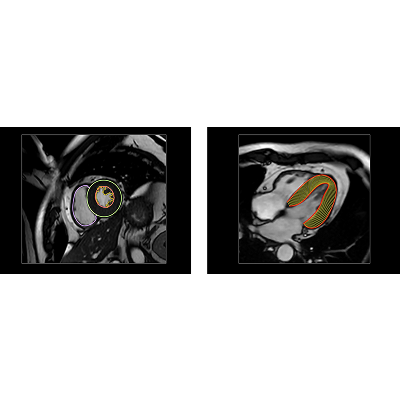

站在医生的角度,联影智能给出的答案是“全自动工作流”。方案内置独家算法,可在数秒内自动对多序列图像(心肌内外膜,水肿、延迟强化区域等)进行自动分割、特征提取、心肌运动追踪。这也意味着,在AI的加持下,医生无需像传统流程一样进行繁复地点击与操作,而是在医生打开软件之后,即可对AI基于影像自动生成的参数及分析结果进行确认或微调。而这是真正可以解放医生精力的事情。